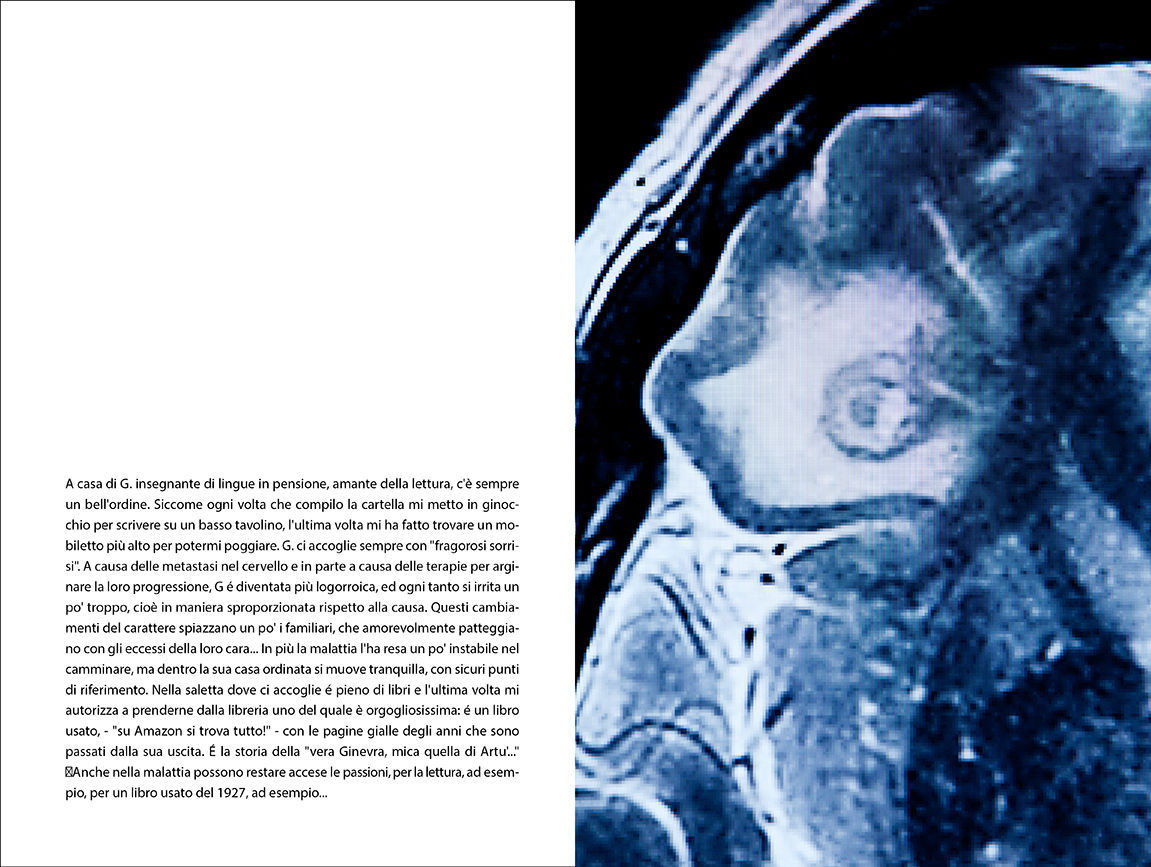

L'opera, dunque, si sviluppa combinando fotografia e testi. L'autore, ha creato un racconto per immagini con l'obiettivo di relazionarsi ed "elaborare" concettualmente attraverso la propria sensibilità i testi della dottoressa. In questa visione, Kairos, approfondisce ed estende la relazione tra fotografie e testi mediante tre tipologie di immagini: still life e immagine di ambiente che hanno come soggetto la professione della dottoressa e le cure palliative; fotografie che riprendono il concetto sulle "eterotopie" di Foucault, inteso come "spazi altri", luoghi reali separati dal normale contesto quotidiano. Questi spazi, secondo Foucault, sono luoghi senza luoghi divisi dal resto del mondo nello spazio e nel tempo. Questi elementi che si ripetono quasi all'infinito raccontano la sospensione di un esistenza. Infine, immagini legate o ispirate direttamente dai testi.

Da un punto di vista del linguaggio, l'autore, consapevolmente e volutamente, nonostante la ricerca racconti l'Uomo, decide la sua totale ed esplicita assenza nelle immagini realizzando fotografie concettuali intensamente evocative, allusive, metaforiche, lasciando così allo spettatore la possibilità di elaborare le proprie suggestioni e trovare la propria dimensione all'interno dell'opera.